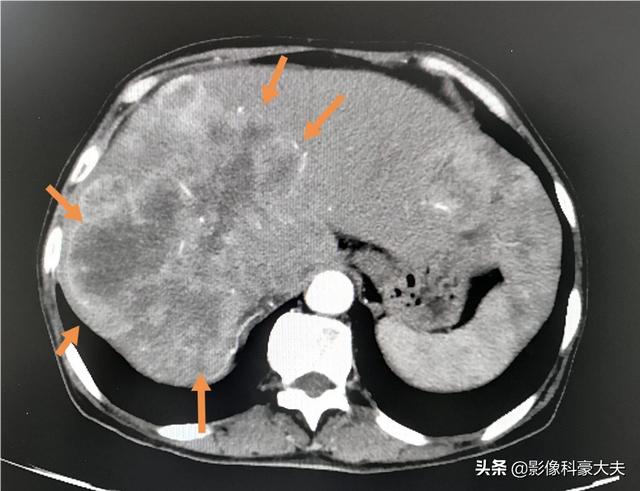

このような巨大な肝転移が多発した場合、コントロールできなかったり、治療に反応しなかったりすると、短期間で進行する可能性がある。